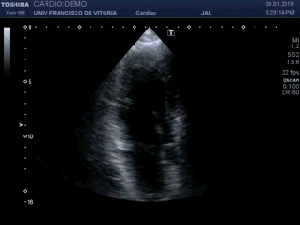

139. Ecocardiografía. Estudio Paraesternal Eje Largo.